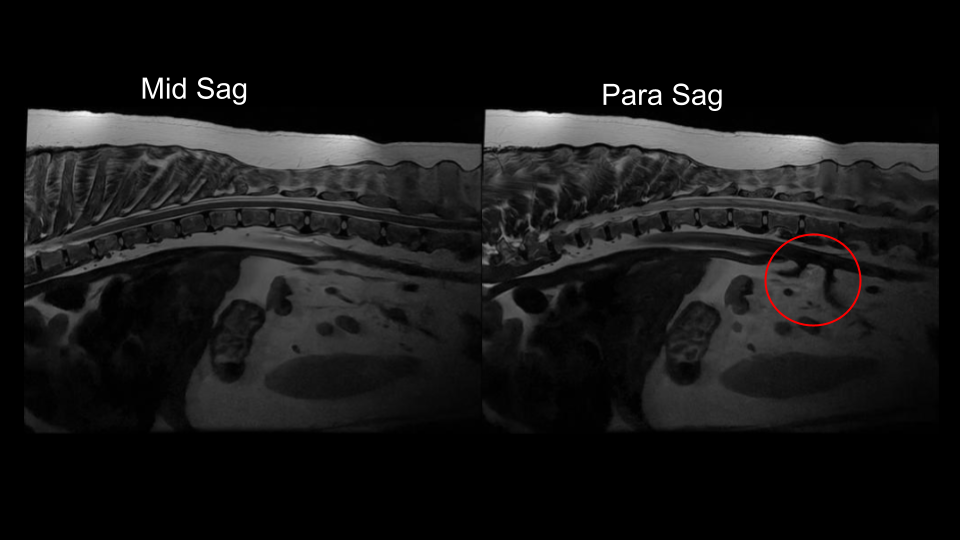

library:mesentericsagthoracic.png

mesentericsagthoracic.png

Back to library:thoracolumbar_spine